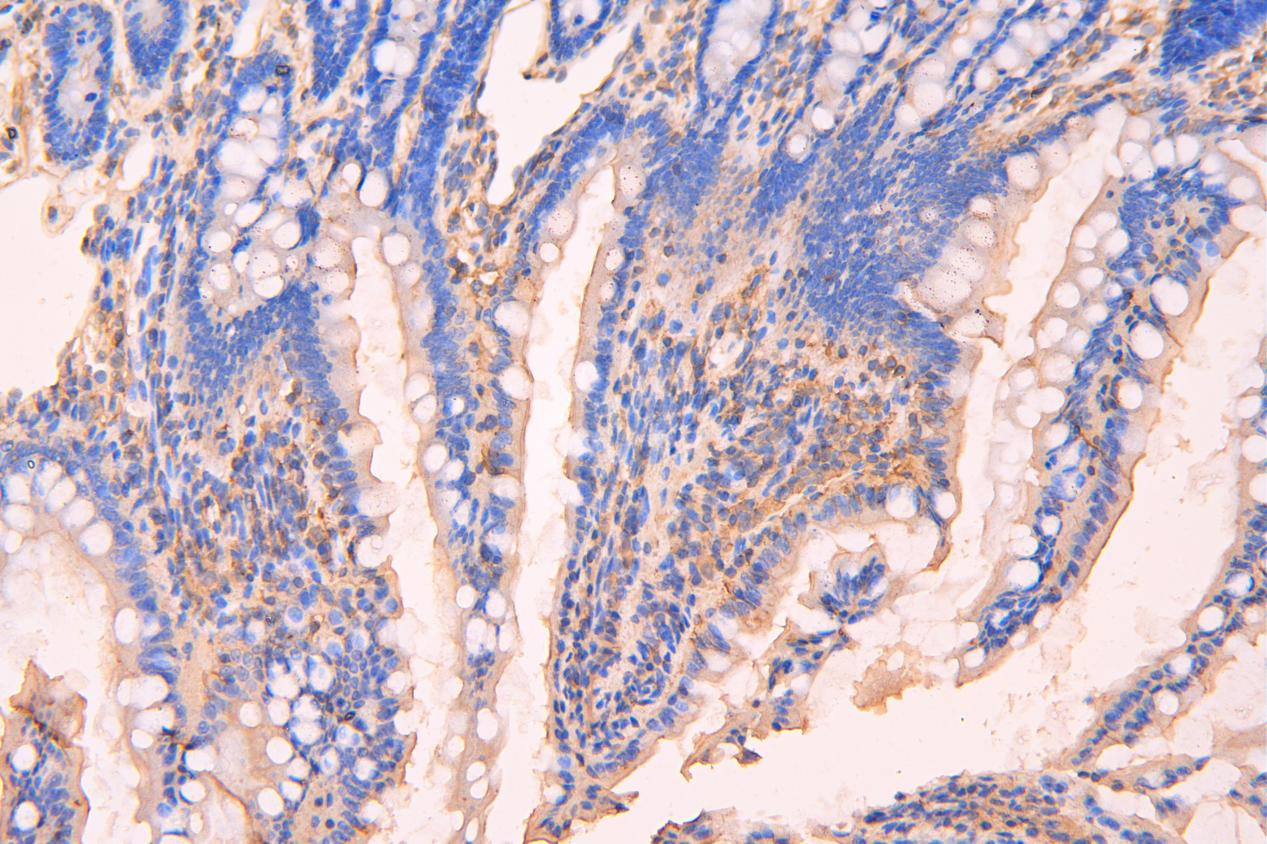

ND4 2D9大鼠腸組織200倍

ND4 2D9小鼠腸組織200倍